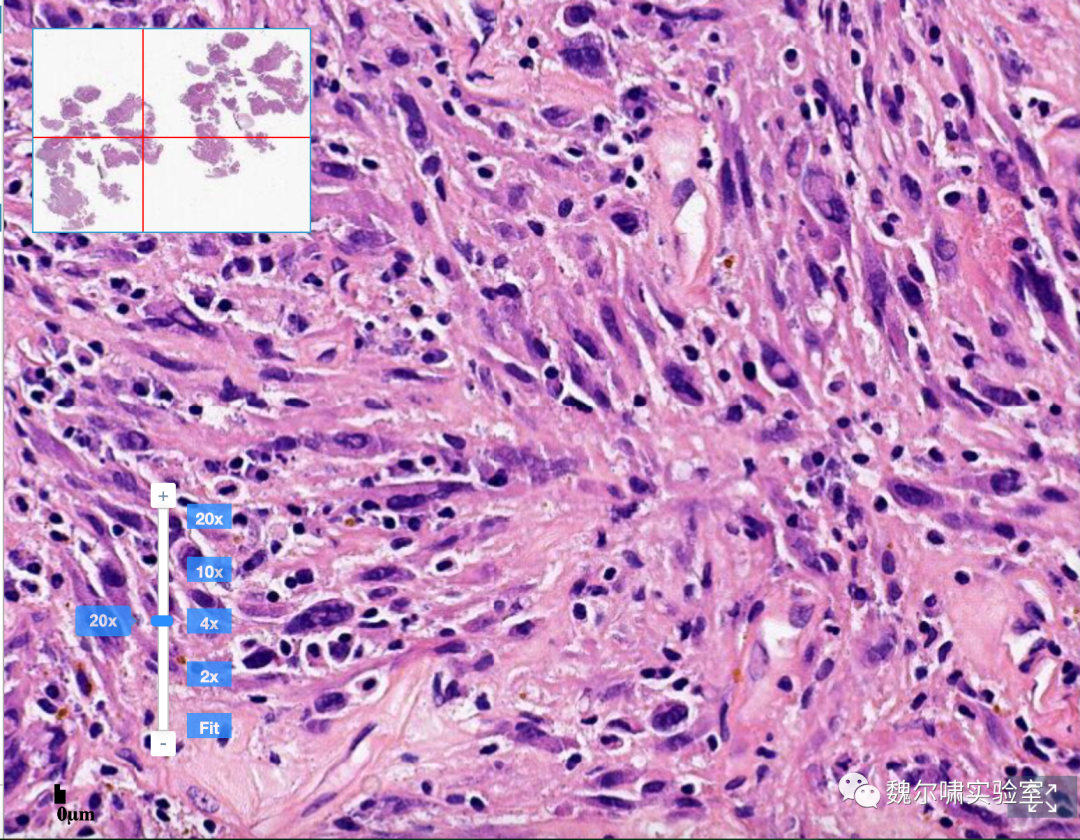

镜下形态显示,根据目前的组织活检,可见浸润性生长:髓内浸润性生长(髓内空间被取代,包围并侵袭原生骨小梁,填充哈弗氏系统),骨皮质破坏伴软组织浸润;肿瘤细胞:显著异型性(多形性,深染),可见多种细胞形态。多种细胞形态通常存在于一种肿瘤内(上皮样,浆细胞样,梭形,小圆形细胞,透明细胞,肿瘤巨细胞)。

最终诊断结果为普通型骨肉瘤(高级别)-建议增加其他染色,通常至少为局部阳性:S100,骨钙素,CD99,SMA;阴性:CD31。